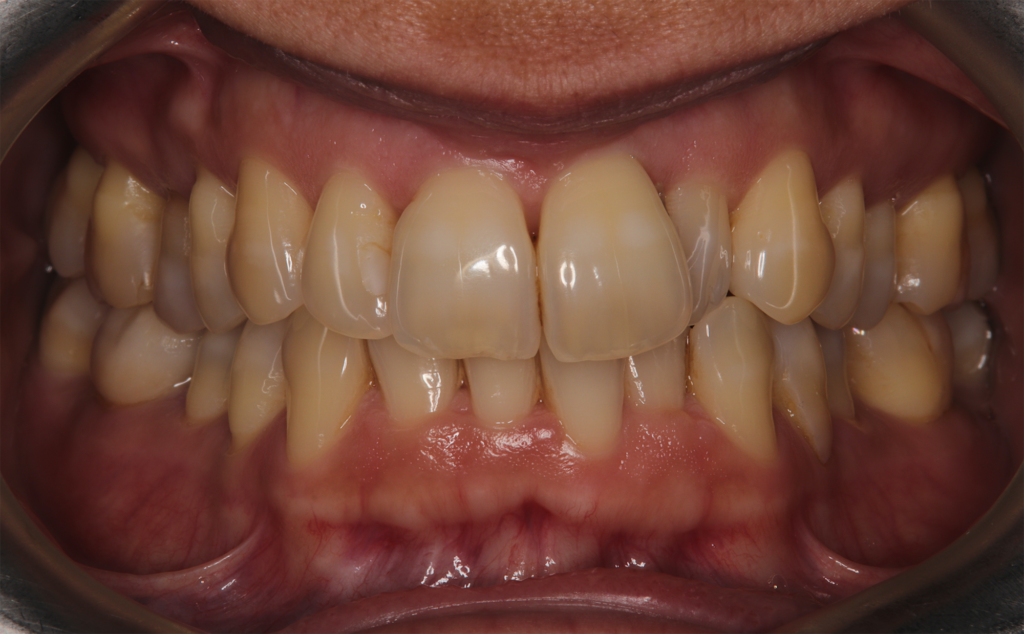

Orthodontic treatment in adult patients who have completed periodontal therapy presents specific challenges. Recent clinical strategies advocate for a slower treatment approach—with reduced force levels and extended phases—to ensure occlusal stability and maintain tissue health. This case report details the management of a patient with lower crowding and an anterior crossbite after a successful periodontal treatment phase, using a moderated treatment velocity to achieve stable, favorable outcomes.

Case diagnosis

The patient, having completed a periodontal treatment phase, presented with significant aesthetic and functional concerns due to moderate crowding in both arches and a pronounced anterior crossbite. Clinical examination confirmed the need for comprehensive realignment, particularly in the anterior region. Although the patient had a history of periodontal issues, radiographic evaluation showed no signs of active disease. Based on these findings, the treatment plan was designed to carefully modulate orthodontic forces to protect the occlusion and surrounding tissues while addressing the misalignment.